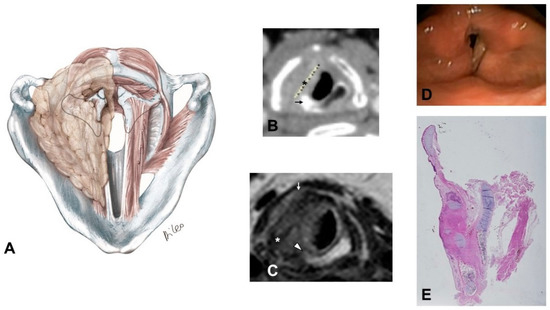

- Glottic-subglottic carcinoma invading the CAJ, and wrapping around it, because the tumor can have type II progression together with CAJ invasion through the conus elasticus with medial to lateral progression (Figure 4):

- The tumor massively involves the IPGS, the thyro-arytenoid space and/or posterior crico-thyroid space and blocks the arytenoid laterally corresponding to the lateral crico-arytenoid muscle, it involves or invades the arytenoid and often the cricoid. Cricoid and CAJ involvement are frequent, through the conus elasticus.

- Infraglottic extension >10 mm, evaluated exactly at the free edge of the TVC midline, with progression toward the posterior commissure.

- It tends to minimally extend upwards toward the SPGS.